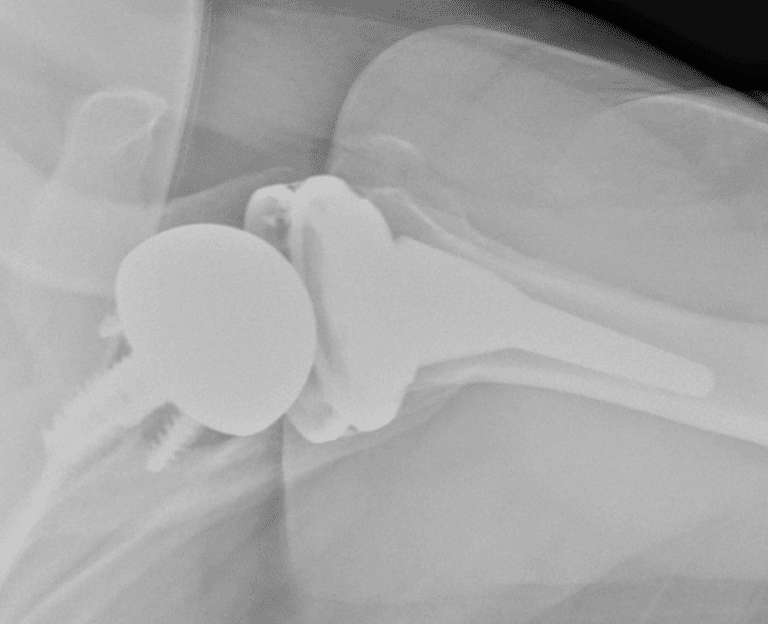

American Shoulder and Elbow Surgeons > Arthrex, MGS

Arthrex, MGS